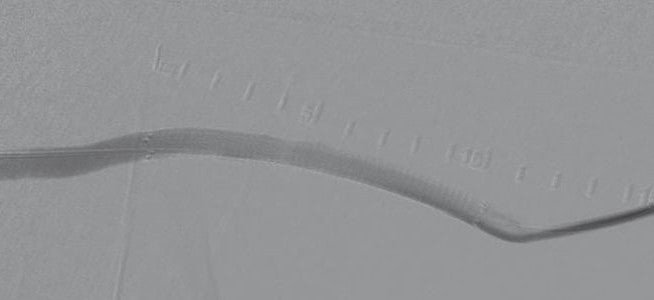

次にステントグラフト内の全長に渡り後拡張を行いバイアバーン® ステントグラフトを人工血管内に圧着した。バルーンカテーテルを挿入時に、バイアバーン® ステントグラフトをカテーテル先端で押し込んでしまうリスクがあるため、透視下に確認しながら挿入した。

最終的に造影検査で良好な血流、挿入位置の確認を行い終了 (図4)。